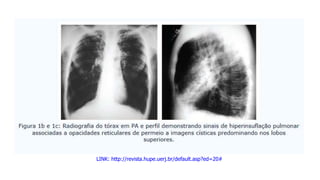

LINK: http://revista.hupe.uerj.br/default.asp?ed=20#

Fibrose Cística